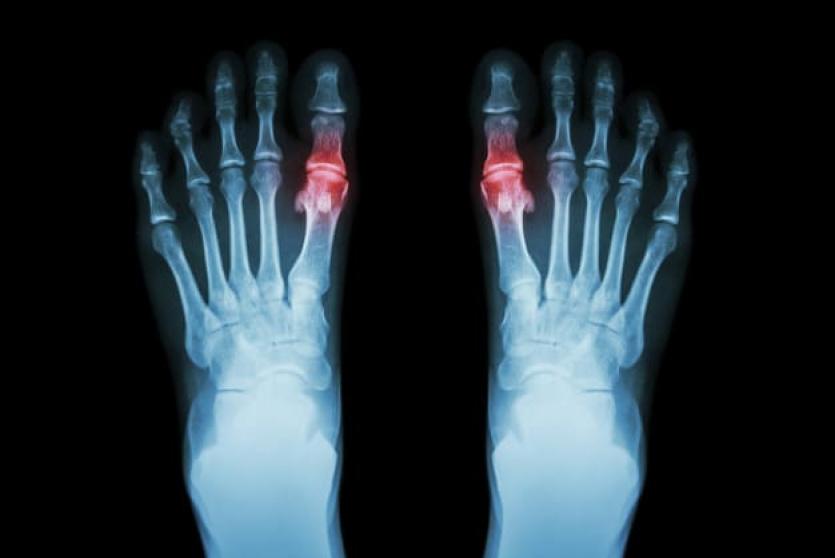

داء الملوك (Gout) أو ما يعرف بالنقرس، هو أحد أنواع التهاب المفاصل (Arthritis) الشائعة الحدوث، الذي عادةً ما يحدث فجأةً في أصبع القدم الكبير مسببًا الام شديدة، من الممكن أن يصيب داء الملوك مفاصل أخرى و يؤثر في المناطق المحيطة بها، مثل الكاحل، الركبة، والقدم.

- ألم شديد في المفاصل: غالبًا ما يكون الألم في أشده في بداية أول أربع ساعات إلى 12 ساعة من الإصابة، وعادةً ما يصيب داء الملوك مفصل الأصبع الكبير من القدم، ولكنه قد يحدث في أي مفصل في الجسم كالكاحل، الركبة، المرفق، المعصم، والأصابع.

- الالتهاب والاحمرار: حيث تصبح المفاصل المصابة متورمة، حساسة، دافئة، ومحمرة.

- التصوير بالأشعة السينية.